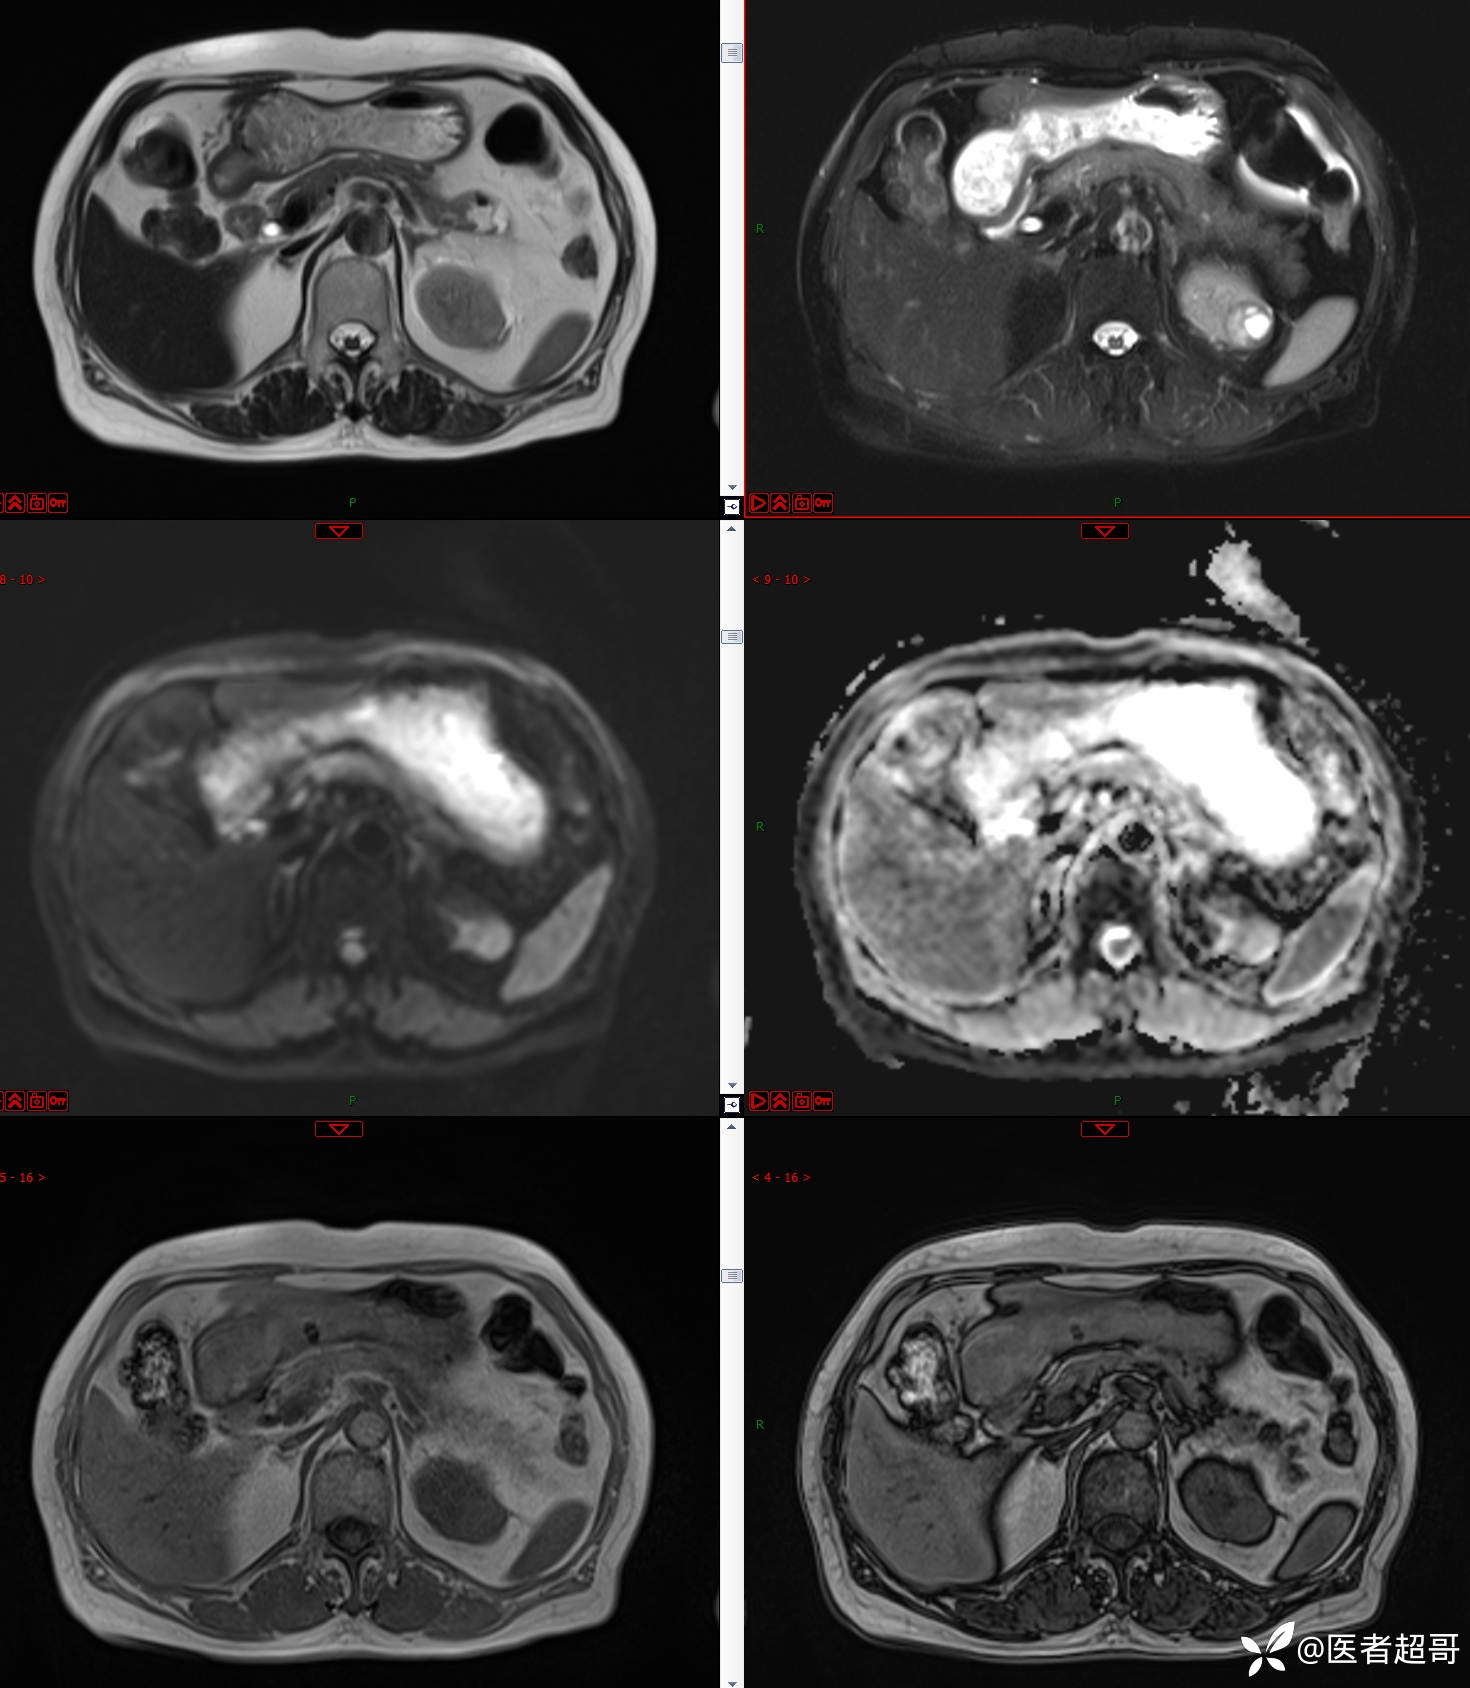

左肾占位2个月就诊,有病理,请分析!

患者 女 73岁

主 诉:查体发现左肾占位2月。

现病史:患者自述2月前于镇中心卫生院行腹部超声发现:左肾实性占位。患者无尿频尿急尿痛,无发热寒战,无恶心呕吐。未行特殊治疗。现患者为求进一步诊治,就诊我院,门诊以“肾肿物”为诊断收入院,患者自发病以来,神志清,精神可,饮食可,睡眠一般,大便正常,体重未见明显改变。